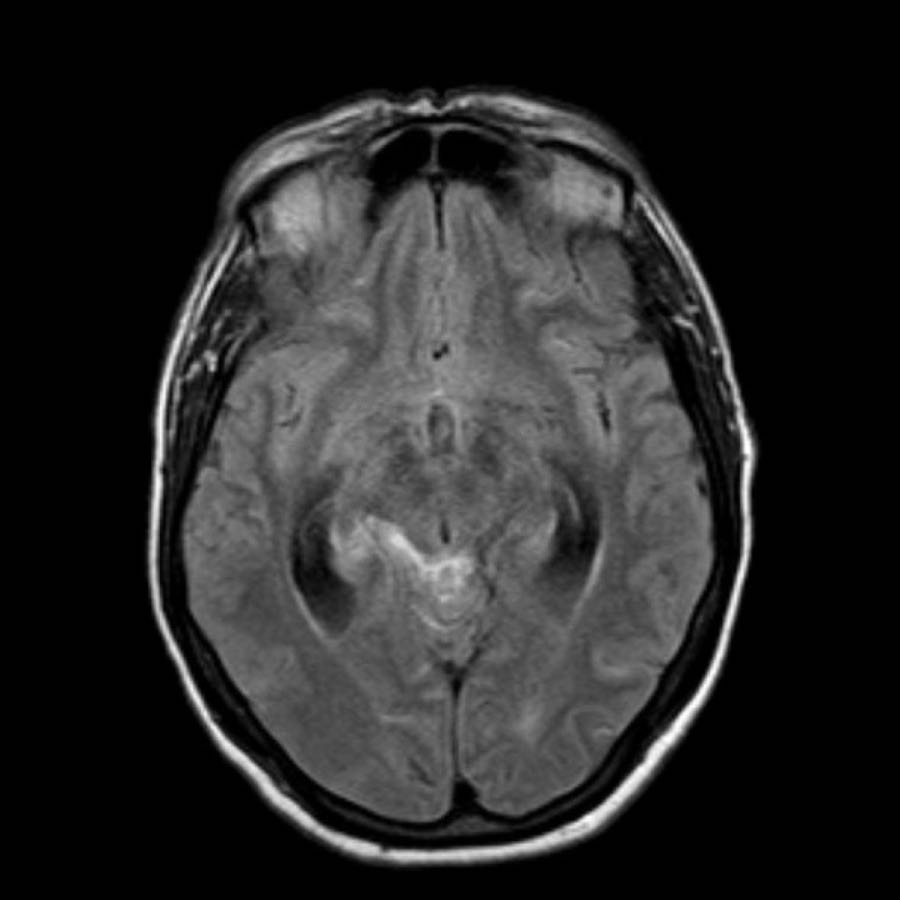

Bệnh nhân này nhập viện với xuất huyết tiểu não.

Các hình ảnh chuỗi xung gradient echo cho thấy nhiều vi xuất huyết.

Đây có thể là hậu quả của tăng huyết áp lâu năm do vị trí trung tâm của một số vi xuất huyết.